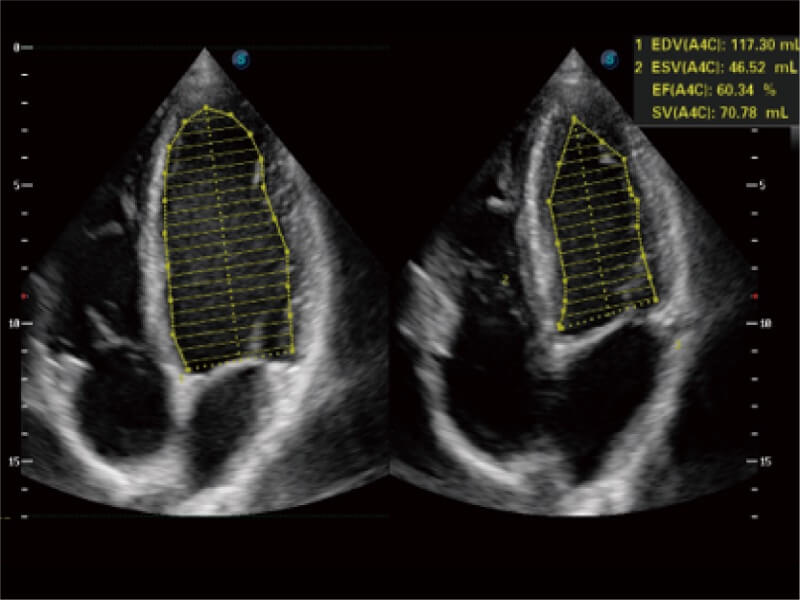

能夠基于左心室壁追蹤和辛普森法,自動計算射血分數(shù),支持多個可移動點描跡,與手動測量相比,極大節(jié)省了動物醫(yī)生的時間和精力。